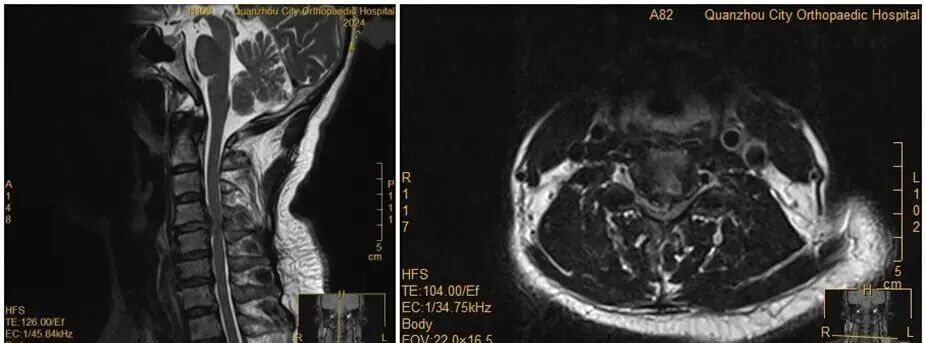

王女士術(shù)前MRI

雖然已經(jīng)出現(xiàn)了癱瘓,王女士仍然懼怕手術(shù),不愿意接受手術(shù)。經(jīng)過(guò)醫(yī)務(wù)團(tuán)隊(duì)及王女士家人耐心解釋及勸解后,王女士才愿意接受手術(shù)治療。醫(yī)院為王女士緊急實(shí)施手術(shù)。手術(shù)順利,經(jīng)過(guò)一段時(shí)間恢復(fù),她的肢體功能逐漸回歸正常。